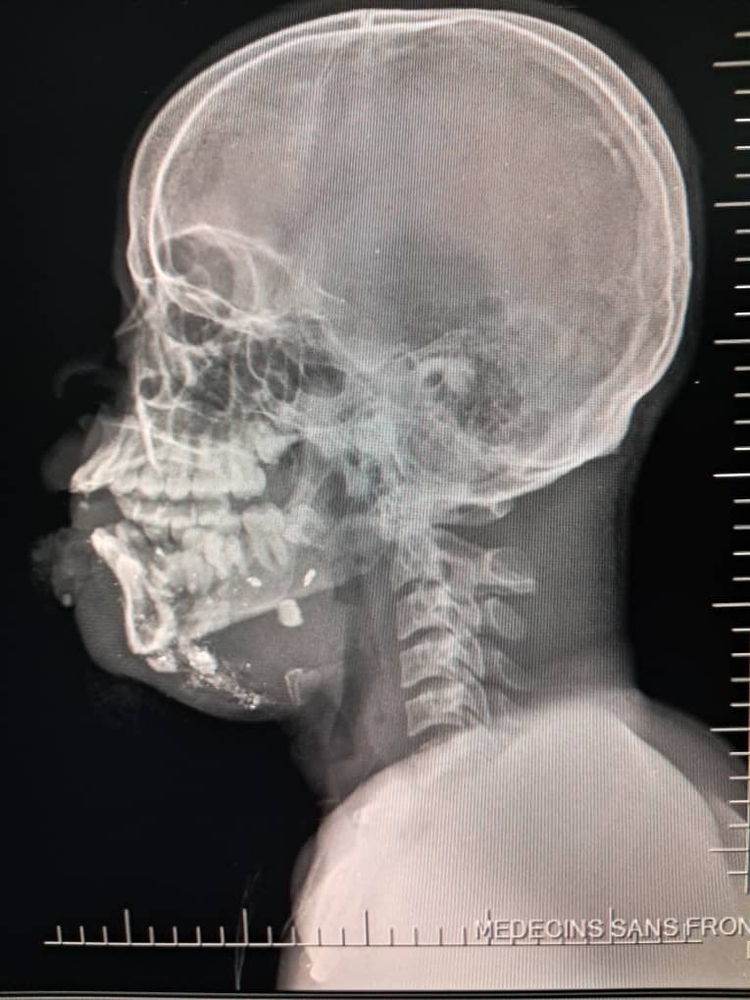

Between January and June 2025, MSF teams assisted 2,600 survivors of sexual violence, admitted 13,300 patients to emergency rooms and treated 2,267 victims of violence. Among these, 26 percent were minors, compared to 11 percent in 2024. Most minors were under the age of 15, and one third were girls. Thirty percent of all minors admitted for violence-related injuries suffered gunshot wounds.

On September 20, 17 wounded people were treated at the MSF hospital in Drouillard following a drone attack carried out the same day in the Cité Soleil neighbourhood. Among these patients, were two men who were already dead on arrival, another man who died while being transferred, ten women—one of whom died en route to MSF’s trauma hospital in Tabarre—and three children who tragically did not survive their injuries. Two more women injured in this attack died at the nearby Isaïe Jeanty maternity hospital, where MSF is also working.

This violence is occurring in the context of a territorial conflict with the population directly on the frontlines, trapped between the threat of explosive drones and the brutal violence of armed groups that loot and burn homes, destroy neighbourhoods, terrorize communities, and increasingly use sexual violence as a weapon of control, punishment, and extortion.